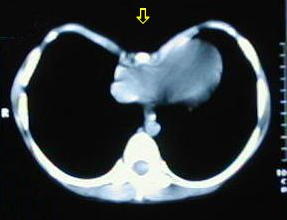

• A medida que descienden los cortes, se observa la mayor depresión esternal.

• A nivel del tercio inferior se observa el punto de máxima depresion esternal.

• Corte a nivel del apéndice sifoides, observe la acentuada depresión por efectos de los cartilagos costales comunes.